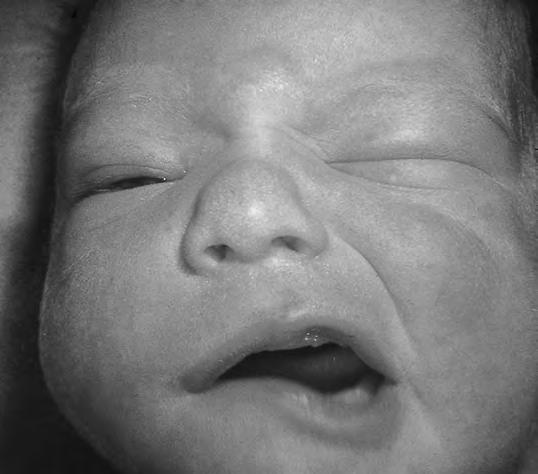

Parálisis facial

Generalmente unilateral, se produce en la mayoría de los casos por compresión sobre la apófisis mastoides de las cucharas del fórceps, o cuando la cara del RN se comprime sobre un resalte óseo materno. Hay una asimetría de la boca, desviando la comisura hacia el lado sano, apreciable fundamentalmente cuando el niño llora, lo cual se conoce clásicamente como signo de Pitres. En casos más intensos existe evidente asimetría en los pliegues y, si afecta al facial en todas sus ramas, dificultad para cerrar el ojo (Fig. 2.29.5). En la mayoría de los casos es benigna y regresa en el curso de 3 a 4 semanas, muchas veces sin tratamiento. Hay casos más graves y duraderos, lo que depende de la intensidad y naturaleza del trastorno traumático del nervio, que va desde la contusión simple hasta la sección total; de ahí que sea útil, sobre todo para el pronóstico, utilizar la EMG. Cuando la lesión afecta selectivamente al nervio aurículo-temporal se produce el síndrome de Frey: episodios recurrentes de sudoración y enrojecimiento facial por estímulos gustatorios.